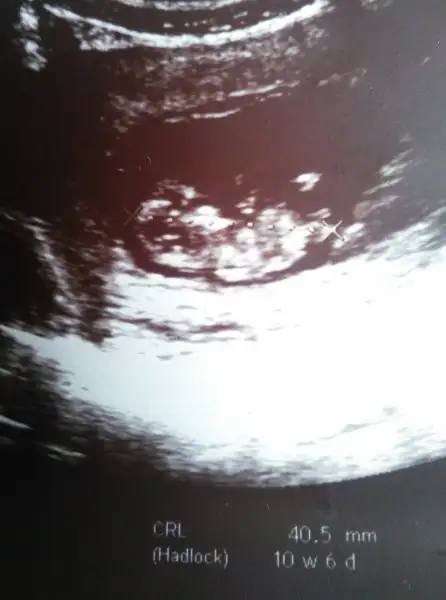

Aa canım ne yaptın cinsiyet tahmininde bulundun muKuzum gene bat a Gore küçük çıktı 11+2 yım bugn ama 10+6 ckti en son 4 gün gerideydi bukez 3 gün geride ilk başta 6 gün gerideydi demk ki yavaş yavaş ileri geliyor :) sna cinsiyet tahmini yaptımi

Geçen gittiğimde benim de gerideydi bu sefer ileri gitmiş iki gün doktor iki üç güne takılma bu ayla uyumlu dedi ya ona bak dedi , seninki de yavaş yavaş yetişecek, ya cinsiyet için erken dedi sonra yalancı çıkarım dedi:) senin yaptı mı ? Bi de hani yeğenimin resmi görmedim onu:)Kuzum gene bat a Gore küçük çıktı 11+2 yım bugn ama 10+6 ckti en son 4 gün gerideydi bukez 3 gün geride ilk başta 6 gün gerideydi demk ki yavaş yavaş ileri geliyor :) sna cinsiyet tahmini yaptımi

Ayyy çok heyecanlı :) Senin adına çok sevindim bebeğini gördün :) Ölçümleri de yapılmış darısı basima cumartesi kontrolum tam 12 haftalık olacak inşallah bakalım bir tahmin duyabilecekmiyiz inşallah :) Oğlum kardeşini çok merak ediyor ona isim vermiş kendi kendine en sevdiği meyve olduğu için herhalde Kivi diyor :) Bakalım sabırsızlıkla hafta sonunu bekliyoruz.Doktor bir tahminde bulundu mu size ama daha erken söylememiş olma ihtimali yüksek..Allahim sağ salim doğurmayı nasip etsin hepimize...Amin canm yagit bakalm ne diyecek . İnslh iyidir . Ense ölçümü ve burun ölçümü yaptı 2li testide sordu yaptırmak istiyormusun dedi bnde yok dedm :)

Bna tam bir tahmin değilde br çıknti var erkek olma ihtimali yüksek dedi ama cinsiyeti 16.haftada belli olur dediAa canım ne yaptın cinsiyet tahmininde bulundun mu

Bna çıkıntı var gbi erkek ihtimali yüksek dedi oran vermedi ama smdi belli olmaz kesin 16.haftada söylerim dedi. Bacak arasına iyice baktı .Geçen gittiğimde benim de gerideydi bu sefer ileri gitmiş iki gün doktor iki üç güne takılma bu ayla uyumlu dedi ya ona bak dedi , seninki de yavaş yavaş yetişecek, ya cinsiyet için erken dedi sonra yalancı çıkarım dedi:) senin yaptı mı ? Bi de hani yeğenimin resmi görmedim onu:)